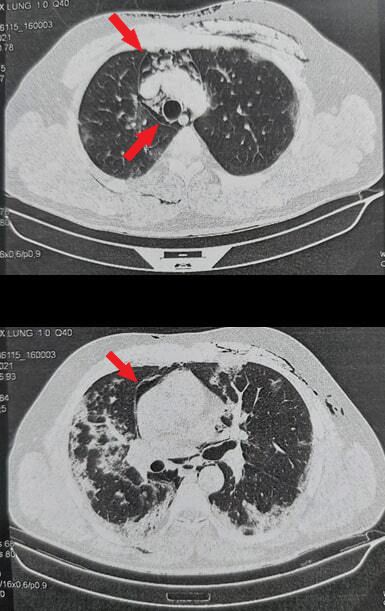

The diagnosis of COVID-19 was confirmed by detection of SARS-CoV-2 nucleic acid in nasopharyngeal swab using Real-Time Polymerase Chain Reaction. Upon admission, thoracic CT-Scan showed bilateral crazy paving appearance affecting 60% of lung parenchyma, with septal thickness in a peripheral distribution.

Four days after admission, the patient presented with tachycardia and cervical tumefaction. Physical examination showed a crepitus on palpation over the neck and an audible crunchy sound on cardiac auscultation. Repeat CT-Scan showed extensive cervical anterior emphysema with pneumomediastinum without pneumothorax (Figure 1 and 2). Cardiothoracic surgery was consulted and they recommended a closely monitoring of the clinical status of the patient. Surgical intervention was unnecessary. The patient was observed and his respiratory status improved slowly but continuously. The oxygen requirements decreased. Repeat CT-Scan showed a favourable outcome (Figure 3).